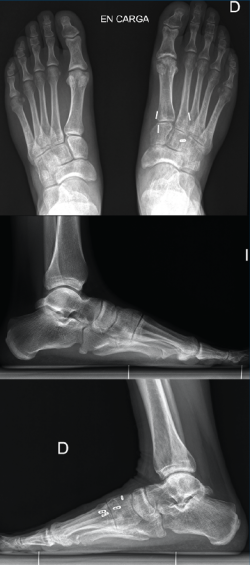

Figura 4. Caso 2. Radiografías lateral y anteroposterior sin carga de control tras la cirugía con fijación no rígida.

Se realiza cirugía con 2 suturas intraóseas C1-M2 y C2-M1 mediante la técnica descrita anteriormente (Figura 4). Se siguió un protocolo posquirúrgico igual al del caso anterior: revisión de la herida a los 10 días, descarga hasta las 6 semanas, carga parcial hasta las 8 semanas con bota y comenzar la carga completa con calzado cómodo con plantilla con soporte de arco longitudinal interno hasta un año postoperatorio.

La revisión a los 3 meses mostró resultados satisfactorios en ambos casos, con tolerancia de la carga completa. Además, las imágenes radiológicas demostraron el mantenimiento de la reducción conseguida en el quirófano, sin movilización del material (Figuras 5 y 6).

Figura 6. Resultados radiográficos posquirúrgicos en el caso 2.